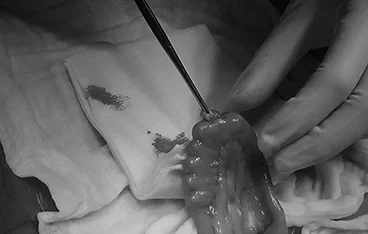

GDV

위염전 해소, 비장절제술, 위고정술(재발 방지)

• 위염전 해소

• 비장절제술

• 위고정술(재발 방지)